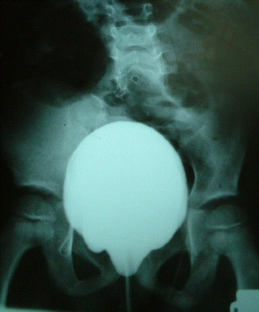

Fig. 1